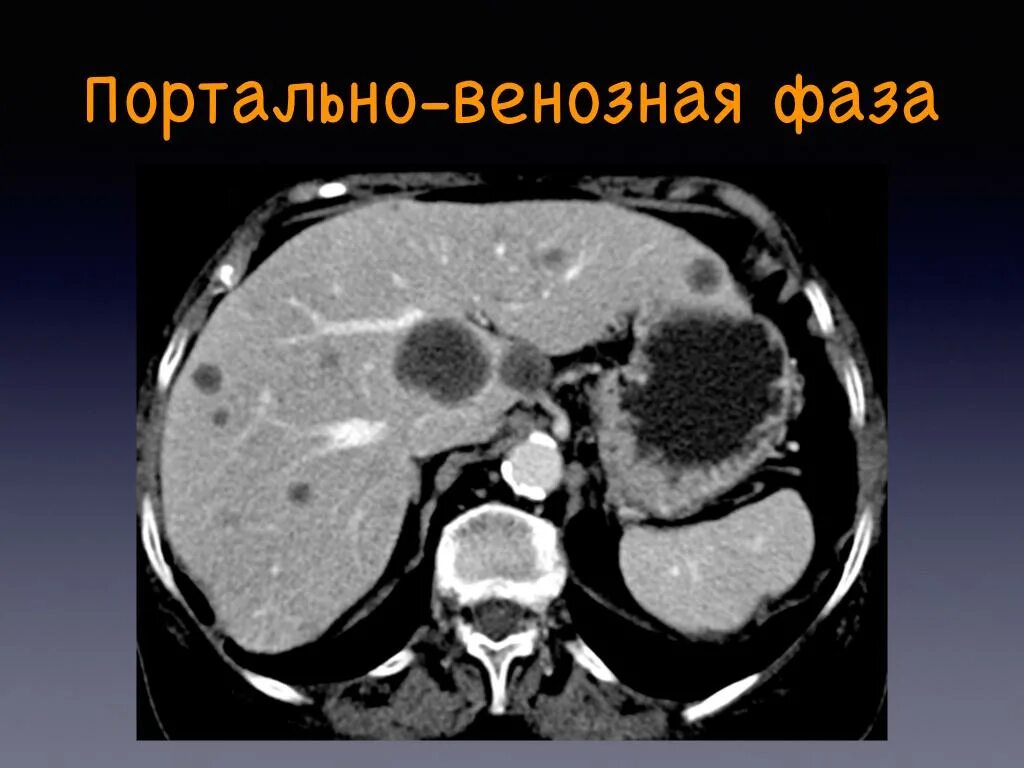

Фазы кт